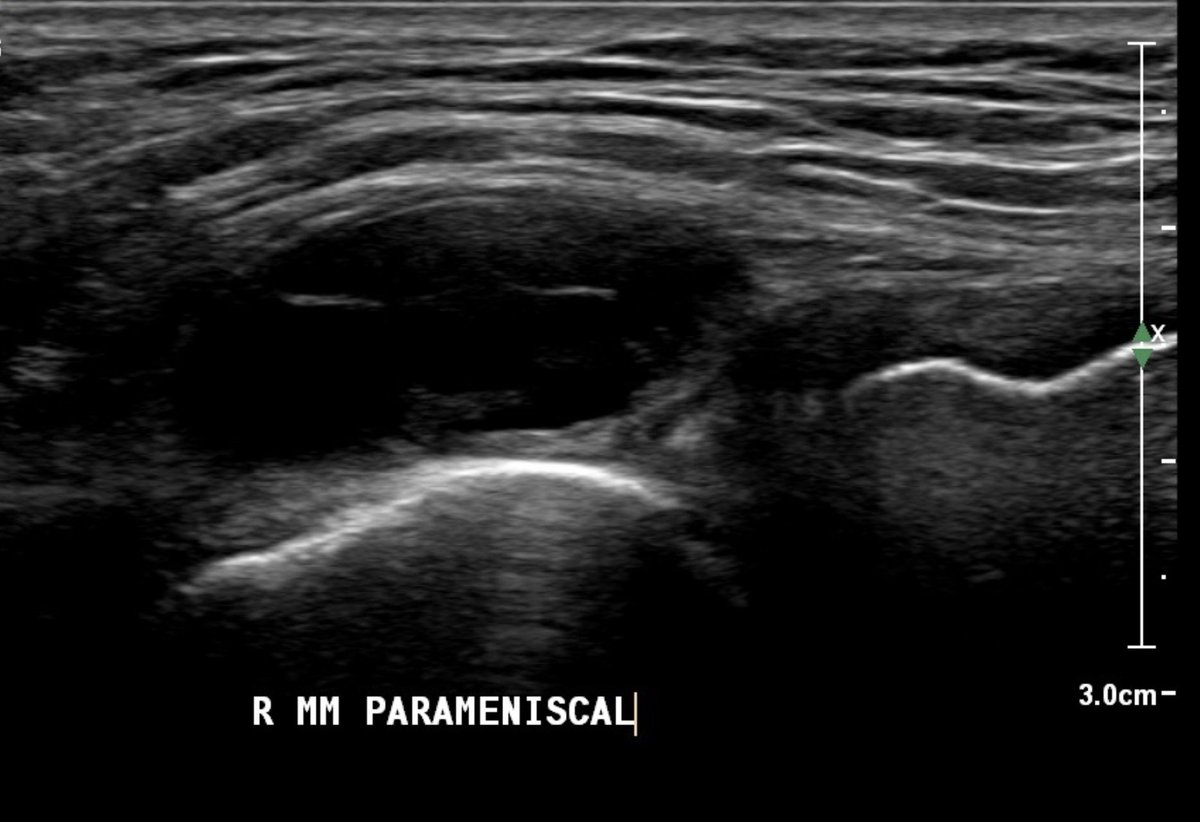

4. Parameniscal cyst

Hx of meniscal injury; tender swelling that fluctuates in size ('barometer of joint mood'!)

Pain on lock out into extension (sometimes 'block' sensation)

Lump size may ⬆️⬇️ palpating on passive ROM

Can aspirate, but often recur - ? scope / open resection